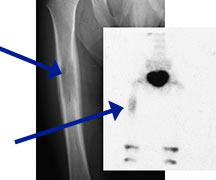

- May arise from any bone and any site within a bone (epiphyseal, metaphyseal, diaphyseal)

- Radiographically variable appearance: may appear benign (geographic) or malignant (permeative or moth eaten)

Sites:

- Femur